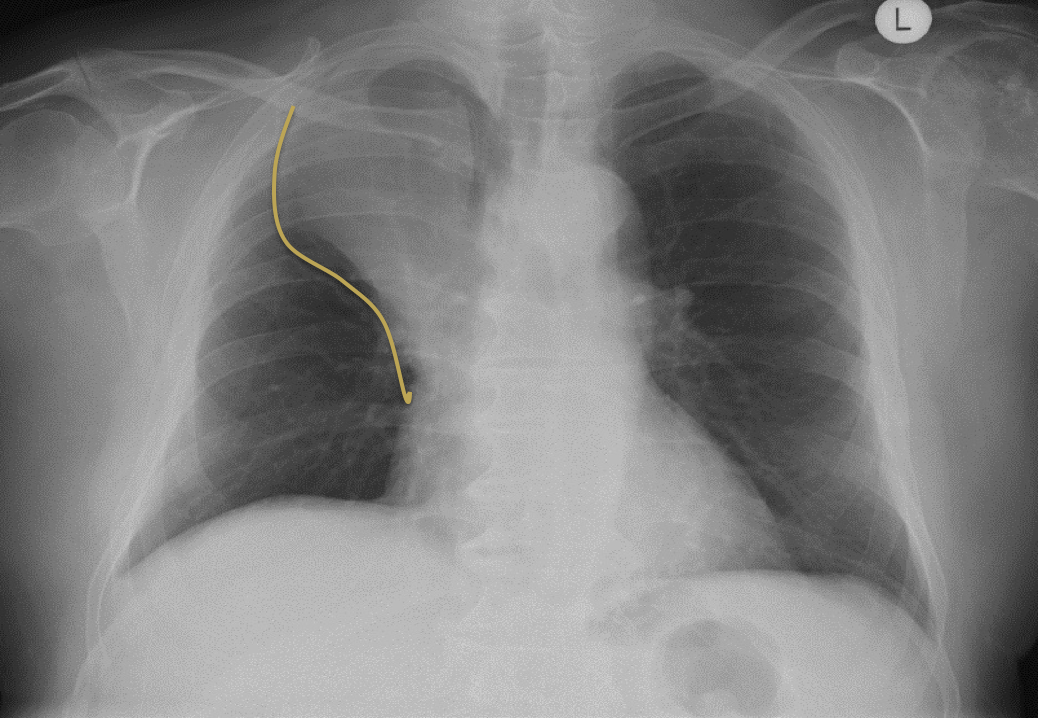

What is this PA CXR showing?

What should you be suspicious of?

Right upper lobe collapse –> Golden S sign

Consider: carcionma. The mass can block the bronchus to right upper lobe causing it to collapse and the lung rotates backwards